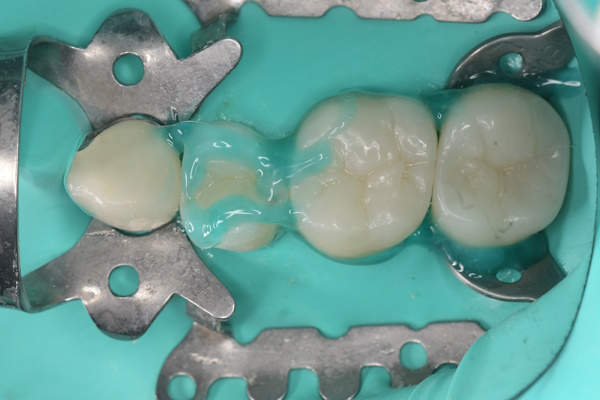

セラミック治療の治療例です。金属の使用を避けたいとのご希望から、メタルフリー治療を目的に来院されました。セラミックは生体親和性が高く、金属を使用しないため金属アレルギーのリスクが少なく、安心して使用できる素材です。当院にて虫歯治療を行い、セラミックによる修復を実施しました。通院回数の負担を考慮し、上下同時での治療をご希望されたため、同日に治療を行っています。接着の精度を高めるため、治療時にはラバーダムを使用しています。また、オキシガードは過酸化物と還元剤による化学重合反応により、歯科接着用レジンセメント表面の未重合層を硬化させる材料です。未重合層を空気から遮断することで確実な硬化を促します。

上顎

術前から術後までの治療の流れ

虫歯処置後

エッチング後

オキシガード使用後

セット後